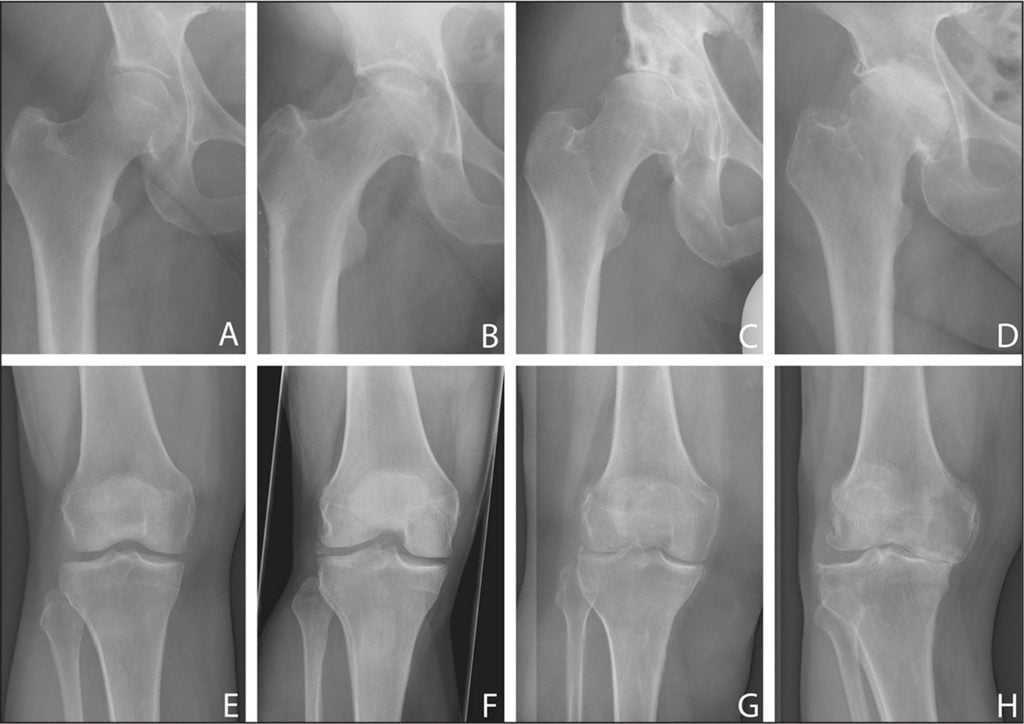

- выраженная деформация сустава и ноги, в целом (связана с изменением конфигурации колена, а также перестройкой мышечного каркаса и искривлением костей);

- укорочение конечности за счет стачивания головок костей;

- анкилоз: полное отсутствие движений в пораженном колене;

- поражение других отделов опорно-двигательной системы из-за неправильного распределения нагрузки (пяточная шпора, артроз тазобедренного сустава, боли в позвоночнике).

Уменьшение суставной щели.

Динамика болезни.